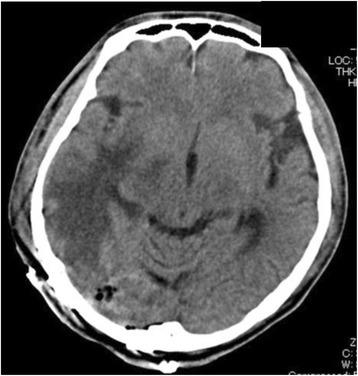

We report a patient who developed sustained hypotension during craniotomy; further, owing to a mediastinal mass, critical tracheal stenosis and brain edema were observed after craniotomy, despite the absence of preoperative symptomatic superior vena cava (SVC) syndrome. A 62-year-old man underwent removal of a suspected metastatic brain tumor. The main brain tumor was speculated to be a metastatic tumor from lung cancer. A subsequent chest CT revealed a large solid tumor in the mediastinum. The maximum reduction in the cross-sectional area of the trachea was estimated to be 50 %. In addition, bilateral innominate veins were completely obstructed, and the superior vena cava was involved in the mass and was completely compressed. The patient did not show any cardiopulmonary symptoms or upper body edema. Intravenous lines were secured at the right extremity. General anesthesia was induced without any complications and was maintained with sevoflurane, remifentanil, and rocuronium. During the surgery, hemodynamic status fluctuated and was unstable. To maintain systolic blood pressure, continuous, massive infusion of noradrenaline was required. After the surgery, the patient was turned to the supine position. Massive facial edema was apparent. In addition, the bilateral upper extremities were significantly swollen. Despite the removal of the main lesion, brain edema was still observed on head CT. Chest CT revealed that the maximum reduction in the cross-sectional area of the trachea was estimated to be >90 %, which necessitated mechanical ventilation with tracheal intubation. On the day following craniotomy, tracheal stenting was performed uneventfully. The patient's trachea was finally extubated, and his respiratory condition did not deteriorate. Although he did not develop SVC syndrome, the patient died from asphyxiation after coughing up blood at home 5 months after the procedure. It was suggested that fluid infusion from the upper extremities owing to the mediastinal tumor caused critical SVC syndrome.